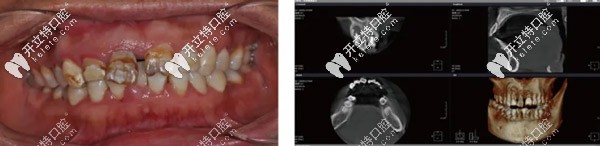

上頜前牙即拔即種聯(lián)合鈦網(wǎng)固定骨粉,采用OsstemTS 3.5*13植體

種植牙奧齒泰即刻種植牙骨粉種植牙發(fā)布時(shí)間: 2025-05-07

本期分享一例上頜前牙即刻種植的案例,聯(lián)合了鈦網(wǎng)固定骨粉,采用韓國奧齒泰TS 3.5*13的種植體。